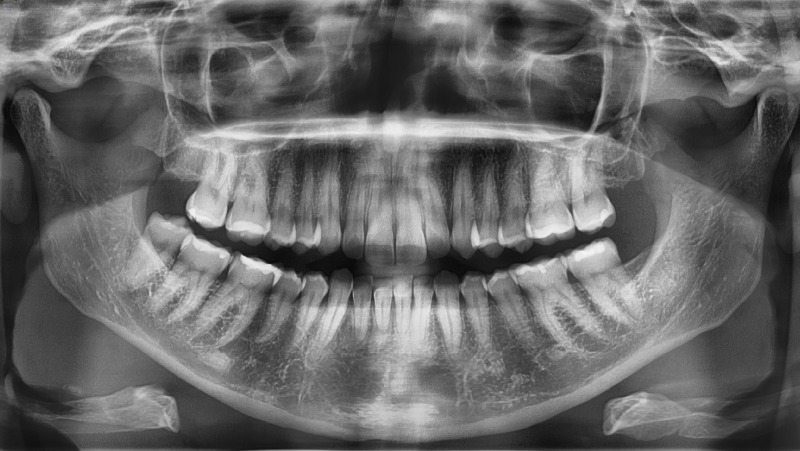

Precizna dentalna dijagnostika uz digitalni ortopan, RVG i CBCT

Točna dijagnoza nezaobilazna je osnova za uspjeh svakog stomatološkog zahvata, bilo da se radi o implantološkim, parodontološkim ili kirurškim tretmanima. Kako bismo osigurali maksimalnu preciznost i sigurnost, koristimo najmodernije dijagnostičke tehnologije, uključujući napredni sustav Planmeca.